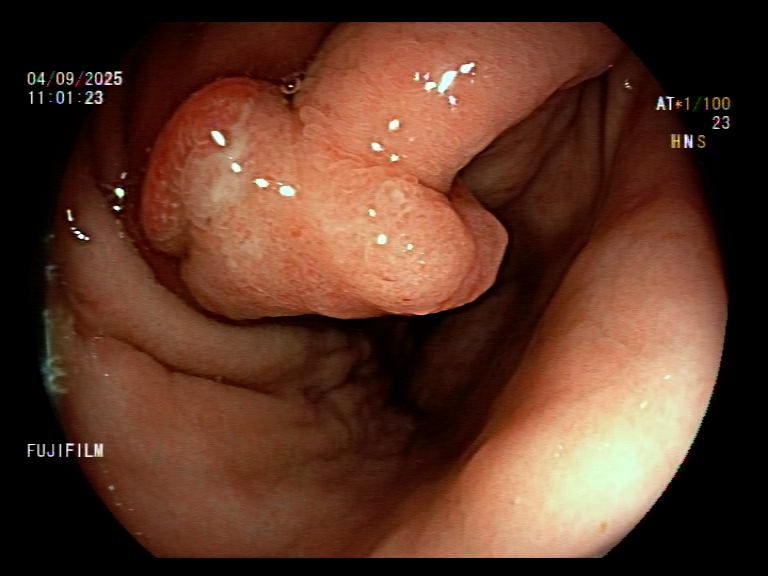

1. Antrum, low grade dysplasia. Removed via ESD. Specimen 43x32mm / dysplasia 20x13mm. R0